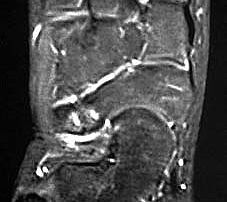

MRT und CT konkurrieren in der Fein-Darstellung der Knochenbrücke, der Beurteilung der nichtbetroffenen Anteile des Subtalargelenkes und der Sekundärveränderungen. Das MRT bietet den Vorzug, bindegewebige und knorpelige Strukturen (Abb. 2) und bei Einsatz von Kontrastmittel auch knöcherne Aktivierungsphänomene genau abzubilden; die knöcherne Feinstruktur und genaue Ausdehnung dagegen ist mit dem Dünnschicht-CT wesentlich exakter darstellbar (Abb.3). In manchen Fällen ist eine 3-D-Rekonstruktion des CT hilfreich. Besonders wichtig ist eine geeignete Schichtebenen-Wahl:

Die zweite wichtige Form tarsaler Coalitiones findet sich im medialen Bereich des Subtalargelenkes, am häufigsten unter Einbeziehung der medialen, mittleren Facette des talocalcanearen Gelenkes (Abb. 9). Die Ausdehnung der zunächst fibrösen, später zunehmend verknöcherten Brückenbildung kann sehr unterschiedlich Anteile der hinteren Kammer des unteren Sprunggelenkes mitumfassen; auch rein dorsomediale Formen ohne Einbeziehung der medialen Facette werden beobachtet (Abb. 2) 67 (Hamel 2008).

Diagnostisch sollte neben Röntgenübersichtsaufnahmen (indirekte radiologische Zeichen: Dorsaler Traktions-Osteophyt am Taluskopf, „talar beaking“; kontinuierliche Linie der Trochlea-tali-Kontur übergehend in die Sustentaculum-tali-Kontur, „C-Zeichen“ (Abb. 11) 10) immer die dreidimensionale Bildgebung eingesetzt werden. Das MRT (mit Kontrastmittel) kann die Struktur der Brückenbildung und z.B. die Qualität des Restgelenkes (Knorpel-Dicke) besonders gut abbilden; das Dünnschicht-CT zeigt die knöcherne Feinstruktur im Bereich der Coalitio und den oft sehr schrägen Spalt-Verlauf im Frontalschnitt dagegen häufig genauer. Meist findet sich die Überbrückung im Bereich der medialen Facette; die Schichten sollten jedoch bis weit nach dorsal beurteilt werden, da ansonsten dorsomediale Formen übersehen werden können. Rozansky et al 7 unterschieden fünf morphologische Typen auf der Basis von 3-D-CT-Rekonstruktionen. Allerdings ist eine prognostische Zuordnung bisher nicht möglich.